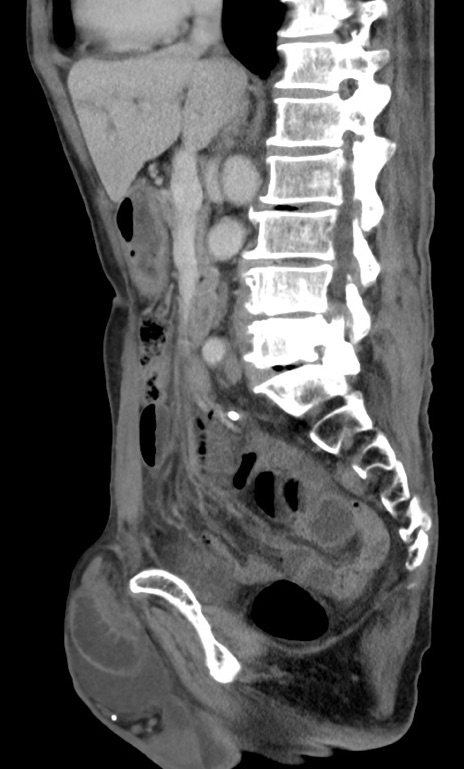

症例3(矢状断像)

【症例】 70歳代男性

【主訴】右鼠径部腫瘤、疼痛

【現病歴】本日朝より上記主訴あり、受診。

【既往歴】膀胱癌にて膀胱全摘、両側尿管皮膚瘻

【データ】WBC 5600、CRP 0.56

横断像

冠状断像